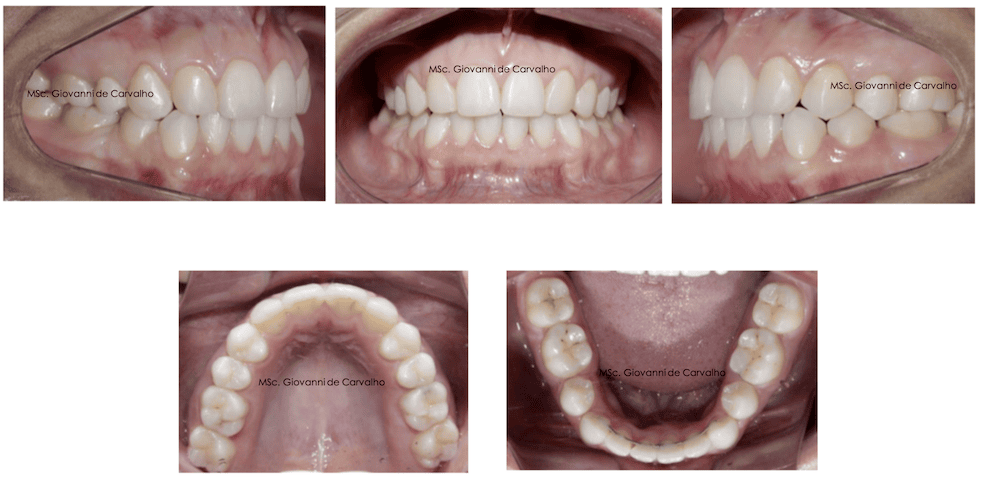

O sorriso da Thaís passou por uma verdadeira transformação. O perfil facial ficou mais equilibrado, com lábios em posição natural e sem esforço. A mordida, antes aberta e invertida, passou a se encaixar corretamente. Os dentes ficaram alinhados, as linhas médias coincidiram e o sorriso ganhou proporção e estética.